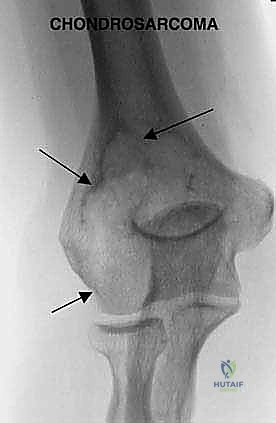

- الساركوما الغضروفية (Chondrosarcoma):

- ينشأ هذا الورم من الخلايا الغضروفية.

- يصيب عادة البالغين وكبار السن (فوق 40 عاماً).

- لا يستجيب جيداً للعلاج الكيميائي أو الإشعاعي، مما يجعل الاستئصال الجراحي الواسع (الذي يبرع فيه د. هطيف) هو العلاج الأساسي والوحيد للشفاء.

- الأشعة السينية (X-rays): الخطوة الأولى التي تظهر التغيرات في بنية العظم، وجود تآكل، أو علامات الكسر المرضي.

- التصوير بالرنين المغناطيسي (MRI): هو المعيار الذهبي. يوضح بدقة متناهية امتداد الورم داخل نخاع العظم، وحجم الكتلة الورمية في الأنسجة الرخوة المحيطة (العضلات)، ومدى قرب الورم من الأعصاب والشرايين الرئيسية.